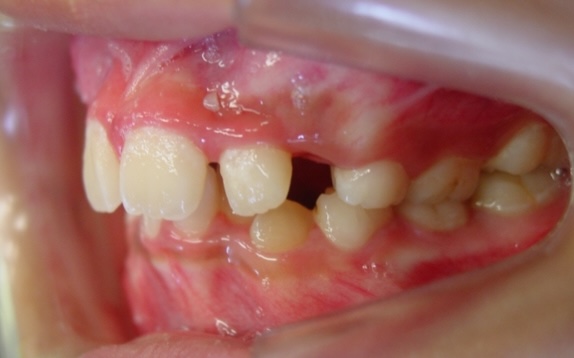

症例1-②

そして、永久歯がすべて生えそろって症例1-②の写真のようになります。上は、軽度の八重歯です。この程度の八重歯は永久歯を抜くことなく治療可能ですが、問題は右下の4番がスペースがまったく無いということです。ここで、一般的な矯正では、右下4番の小臼歯の抜歯と、それに伴う、その他3本の小臼歯の、計4本の永久歯の抜歯を提案されるでしょう。